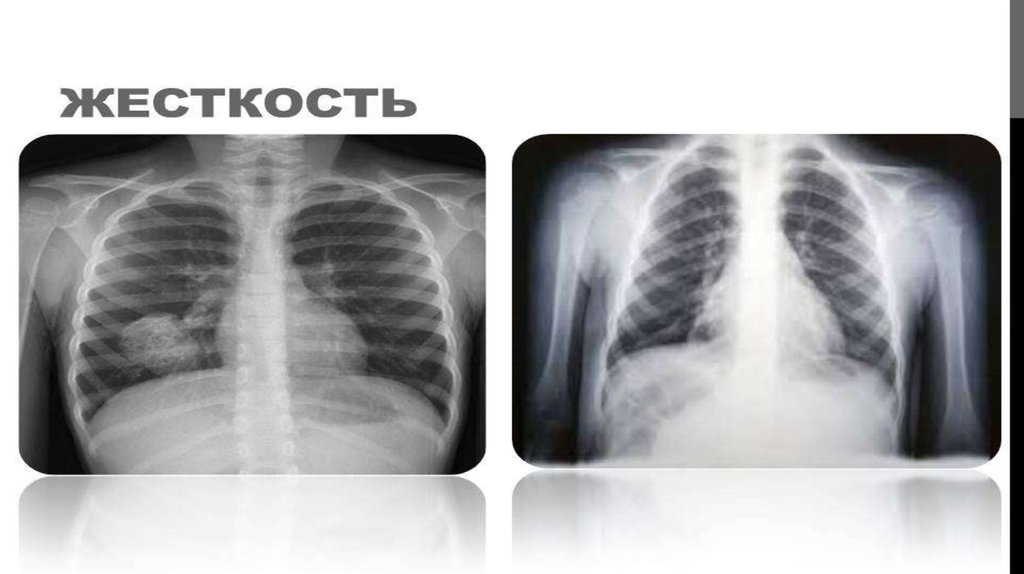

КЕУДЕ ОРГАНДАРЫНЫҢ РЕНТГЕНТ СУРЕТТЕРІ

ИНТЕРПРЕТАЦИЯЛАУ